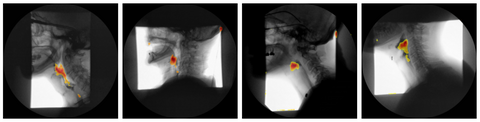

Hesam Abdolmotalleby is the main researcher and lead author on the paper "Detecting Airway Invasion in Variable-Length Videofluoroscopic Swallowing Studies: A Vision Transformer Approach for Oropharyngeal Dysphagia".  Recognizing the burden of manual interpretation for videofluoroscopic swallowing studies (VFSS) in diagnosing dysphagia, this research developed a novel Vision Transformer (ViT) model. The ViT utilizes a temporal sliding window and 3D patch tokenization to robustly capture spatio-temporal dependencies within variable-length VFSS sequences. Evaluated against 1154 VFSS sequences, the ViT achieved an impressive 84.37% accuracy, 90.81% sensitivity, and 79.49% specificity, significantly outperforming several conventional Convolutional Neural Network (CNN) baselines like VGG-16 and ResNet-50. These results highlight the ViT's strong capability for automated VFSS classification, establishing a promising foundation for the clinical deployment of AI-driven tools to streamline dysphagia screening and improve timely abnormality detection.